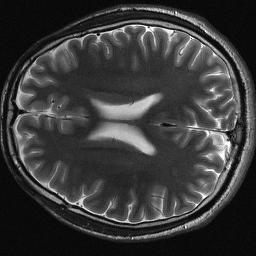

Magnetic resonance imaging serves as an essential tool for clinical diagnosis. However, it suffers from a long acquisition time. The utilization of deep learning, especially the deep generative models, offers aggressive acceleration and better reconstruction in magnetic resonance imaging. Nevertheless, learning the data distribution as prior knowledge and reconstructing the image from limited data remains challenging. In this work, we propose a novel Hankel-k-space generative model (HKGM), which can generate samples from a training set of as little as one k-space data. At the prior learning stage, we first construct a large Hankel matrix from k-space data, then extract multiple structured k-space patches from the large Hankel matrix to capture the internal distribution among different patches. Extracting patches from a Hankel matrix enables the generative model to be learned from redundant and low-rank data space. At the iterative reconstruction stage, it is observed that the desired solution obeys the learned prior knowledge. The intermediate reconstruction solution is updated by taking it as the input of the generative model. The updated result is then alternatively operated by imposing low-rank penalty on its Hankel matrix and data consistency con-strain on the measurement data. Experimental results confirmed that the internal statistics of patches within a single k-space data carry enough information for learning a powerful generative model and provide state-of-the-art reconstruction.